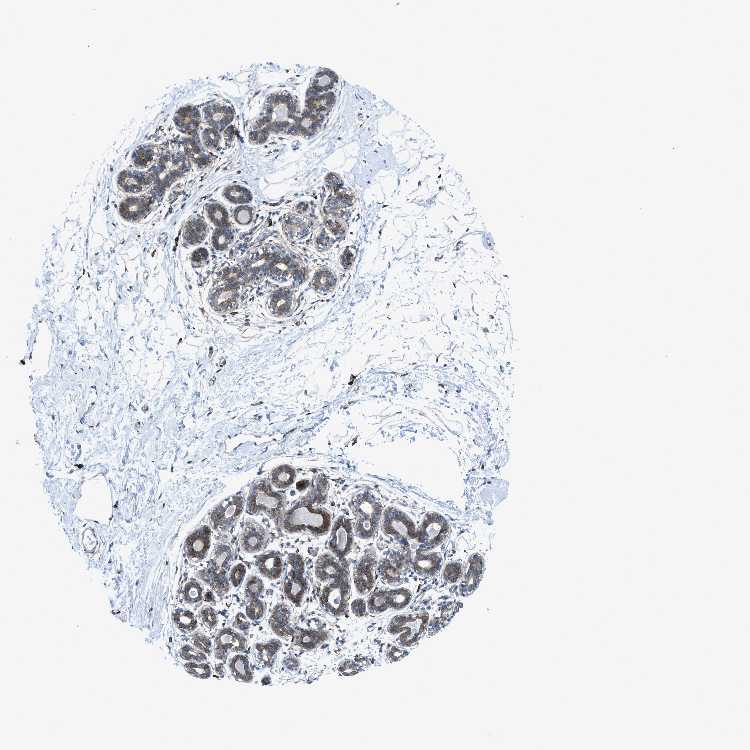

BREAST - Antibody stainingi

Antibody staining in the annotated cell types in the current human tissue is reported as not detected, low, medium, or high, based on conventional immunohistochemistry profiling in selected tissues. This score is based on the combination of the staining intensity and fraction of stained cells.

Each image is clickable and will lead to virtual microscopy that enables deeper exploration of all samples and also displays staining intensity scores, fraction scores and subcellular localization as well as patient and tissue information for each sample.

Antibody HPA001200Antibody HPA018530Antibody CAB000035Antibody CAB068186Antibody CAB073534Antibody CAB080313Antibody CAB080314Antibody CAB080473Antibody CAB080475Antibody CAB080506Antibody CAB080507Antibody CAB080509Antibody CAB080510Antibody CAB080511

Adipocytes Not detectedNot detectedLowNot detectedNot detectedHighMediumLowNot detected-HighNot detectedNot detected-

Glandular cells Not detectedMediumLowNot detectedLowHighNot detectedMediumMediumLowHighLowNot detectedNot detected

Myoepithelial cells Not detectedLowMediumNot detectedNot detectedNot detectedNot detectedMediumNot detectedNot detectedHighNot detectedNot detectedNot detected